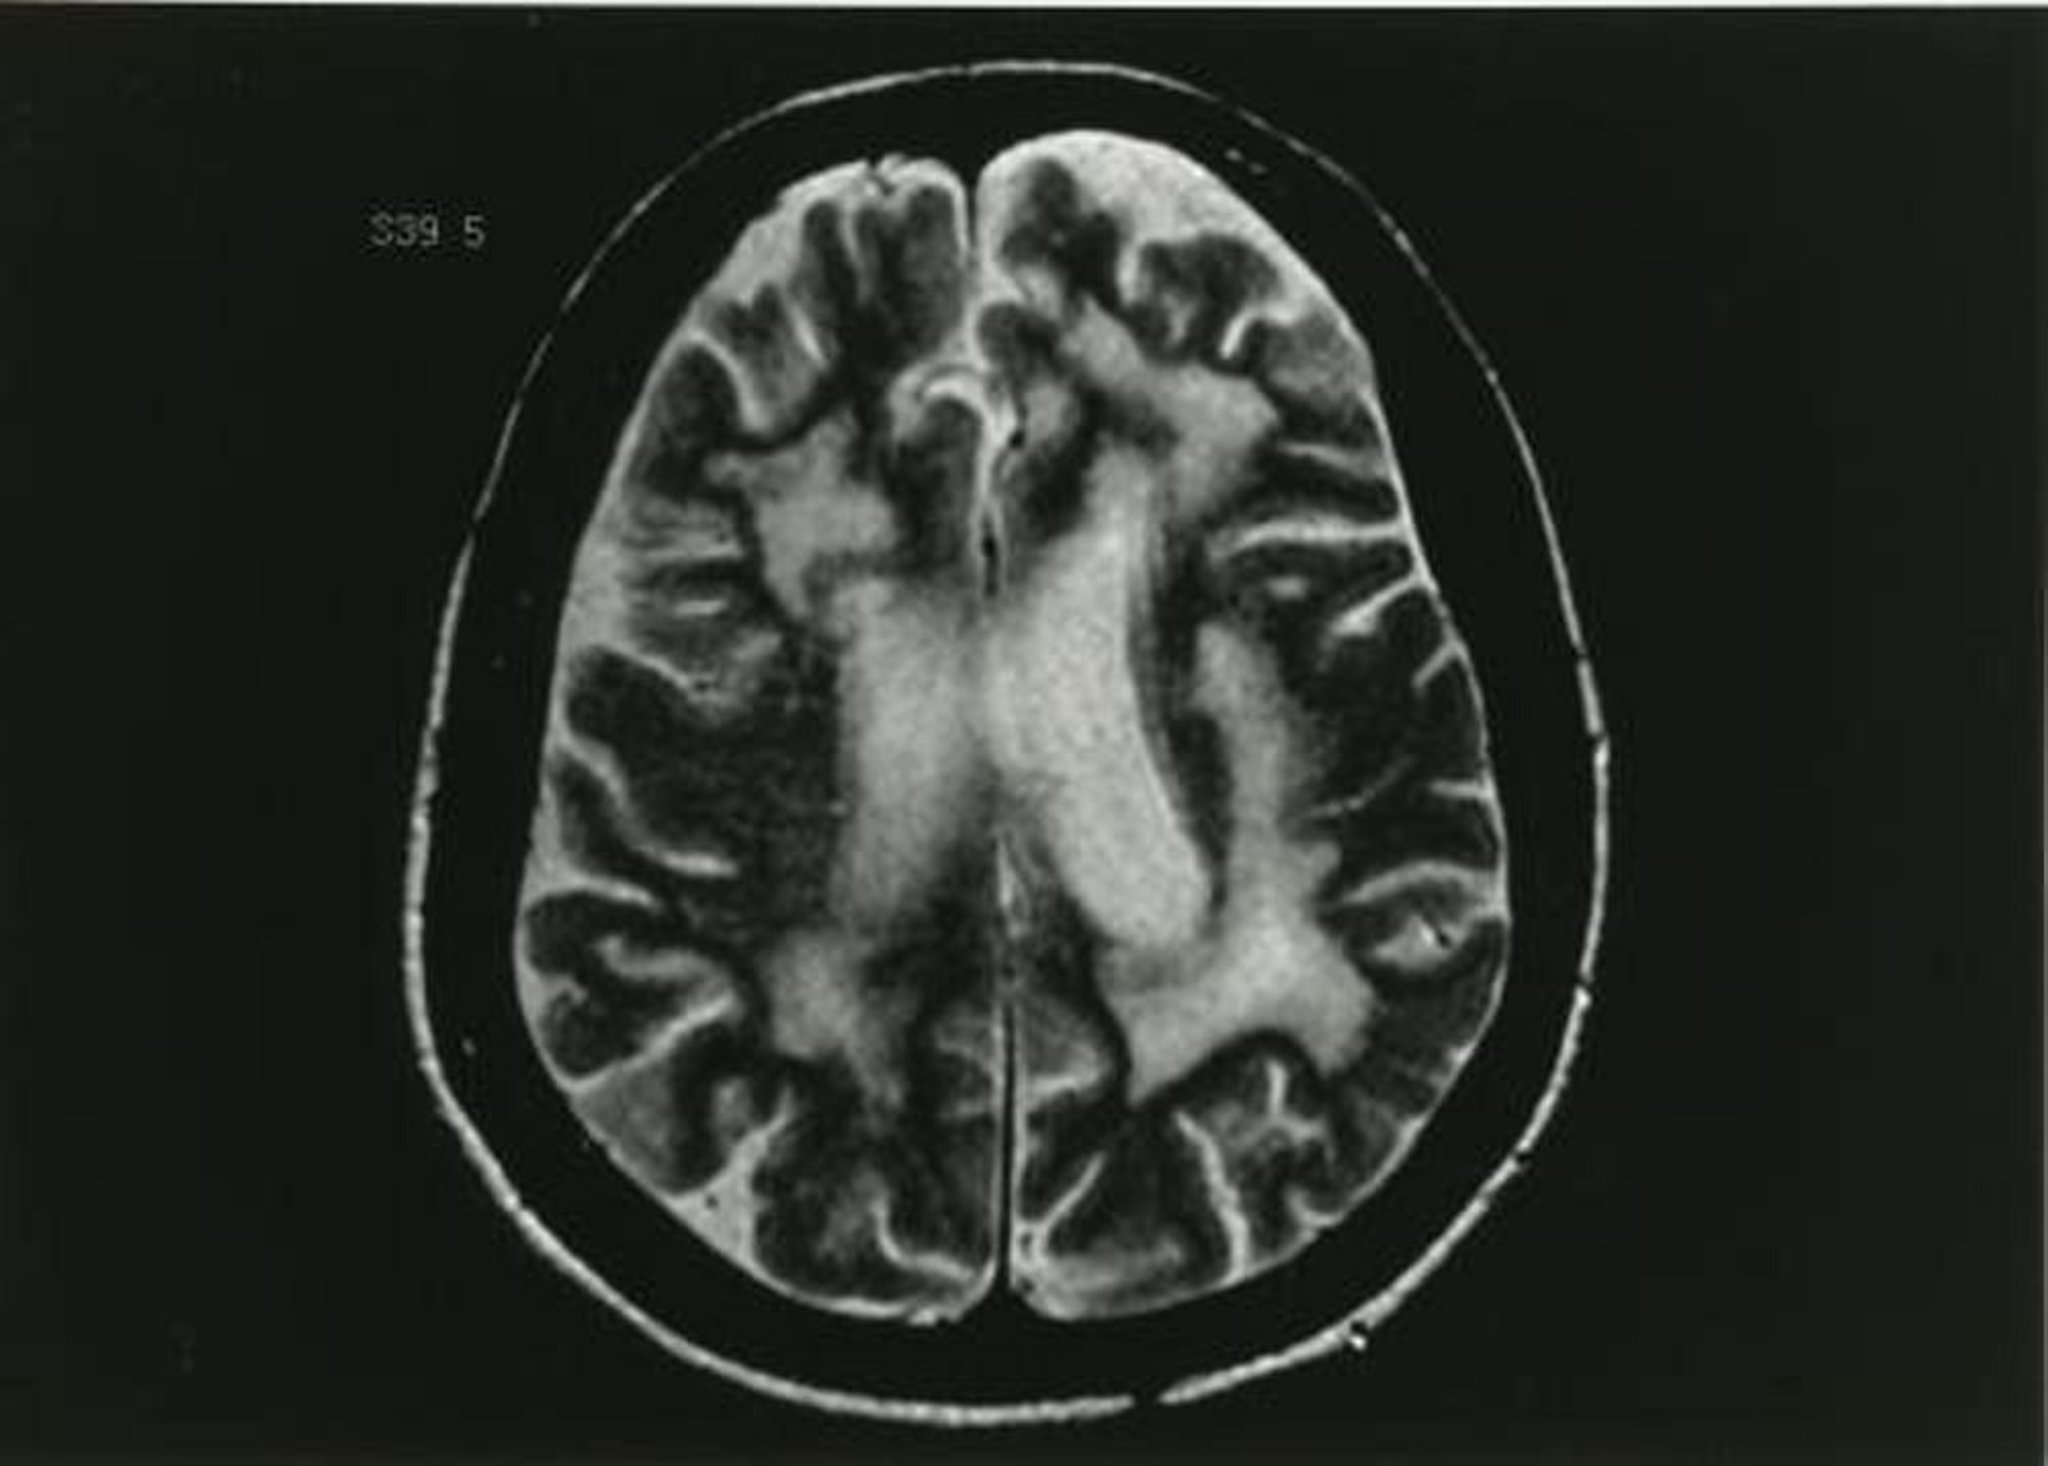

Eine vorläufige Diagnose von PML wird anhand einer Kontrastmittel-MRT gestellt, die einzelne oder mehrere Läsionen der weißen Substanz auf T2-gewichteten Bildern darstellt. Ein Kontrastmittel hebt 5–15% der meist schwachen und peripheren Läsionen hervor. Eine CT kann nichtverstärkte Läsionen mit niedriger Dichte zeigen, ist aber deutlich weniger sensitiv als die MRT.

Dieses T2-gewichtete MRT-Bild zeigt mehrere Veränderungen der weißen Substanz.

Abbildung zur Verfügung gestellt von John E. Greenlee, MD.